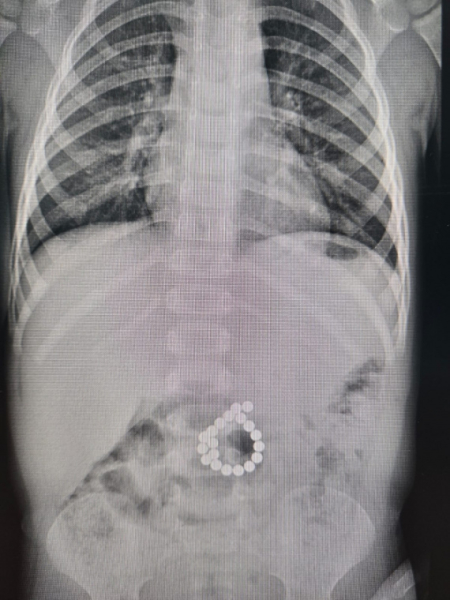

Врачи Сургута спасли малыша, проглотившего 19 магнитов

В Сургуте двухлетний ребенок проглотил 19 магнитов и оказался в реанимации

В Центр охраны материнства и детства Сургута экстренно поступил ребенок двух лет семи месяцев с сильными болями в животе и высокой температурой. Малыш проглотил 19 магнитов от конструктора – из-за этого возникли серьезные повреждения кишечника и воспаление брюшной полости, рассказала в пресс-службе Центра.

Врачебный консилиум принял решение срочно оперировать – проглоченные магниты притянулись друг к другу через стенки кишечника и буквально «прокусили» его.

Экстренную операцию провела бригада под руководством заведующего детским хирургическим отделением Эльнура Джафарова. Во время вмешательства врачи обнаружили двойную перфорацию толстой кишки. Мальчику удалили магниты и ушили поврежденные участки.